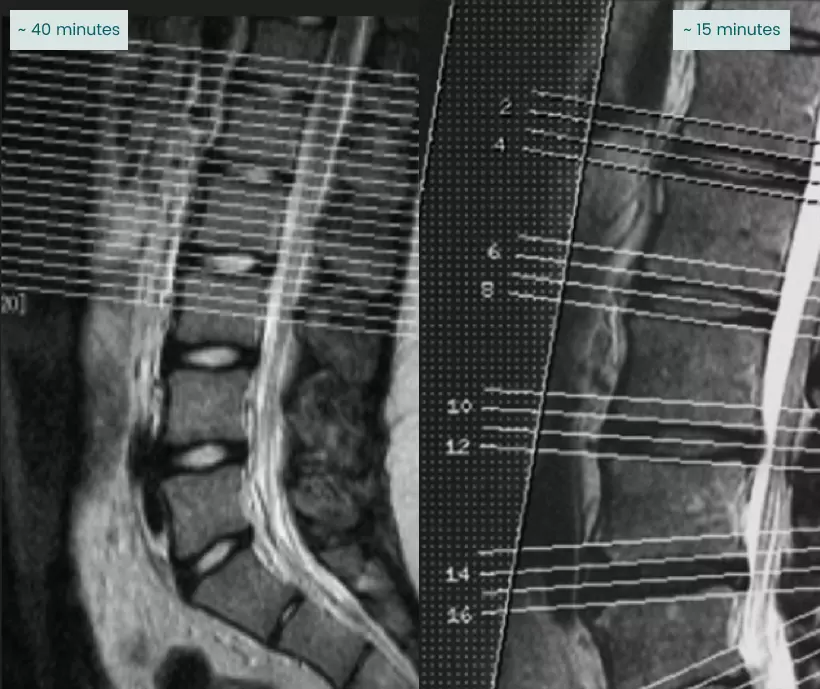

Slide the circle left or right to see how two scanners produce images of the same patient.

Imaging center protocols may prioritize speed over coverage.

When MRI sections are widely spaced, interpretation is more difficult, and radiologists can miss important information.

Widely spaced (~15 minutes)

Narrowly spaced (~40 minutes)